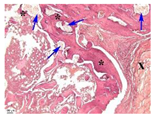

| Point | Type of Microscopy | ||||

|---|---|---|---|---|---|

| Standard Light | Standard Light | Polarization | Standard Light | Phase Contrast | |

| Staining with Hematoxylin–Eosin | Staining with Picrosirius Red | Staining with Picrosirius Red | Staining with Hematoxylin–Eosin | Staining with Hematoxylin–Eosin | |

| 3 | ![]() | ![]() | ![]() | ![]() | ![]() |

| 5 | ![]() | ![]() | ![]() | ![]() | ![]() |

| 8 | ![]() | ![]() | ![]() | ![]() | ![]() |